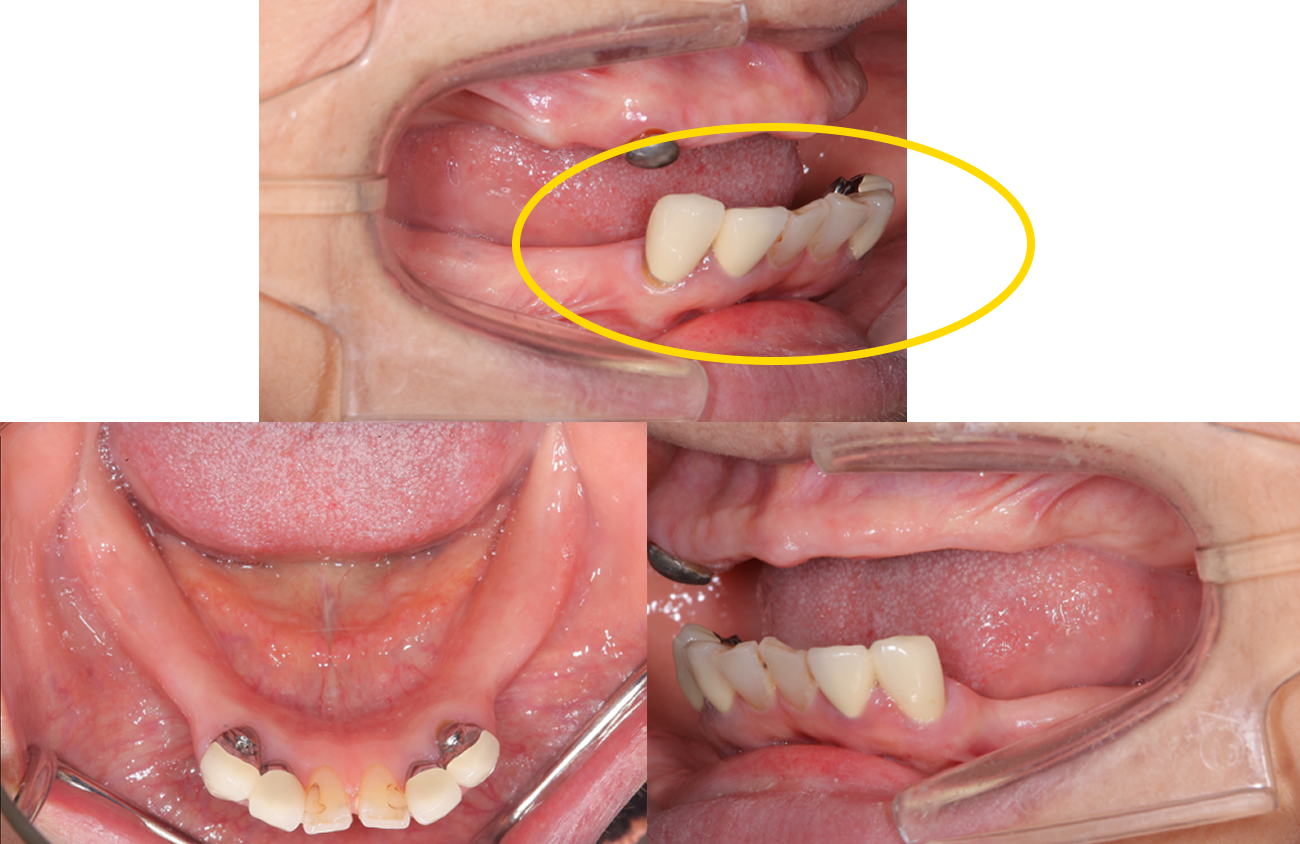

主訴:入れ歯が壊れた。

治療概要:下の入れ歯が壊れたということで来院されました。

よく見ると入れ歯のバネにはゴールドが使用され、上の入れ歯の保険適用外の金属床という入れ歯を使用されておりました。

病的咬合と判断に至った背景

もちろんこのまま入れ歯を作り直すこともできるのですが、入れ歯が壊れた原因を解決しない限りまた割れてしまいます。

診査していくと、入れ歯の強度の問題ではなく、この方の噛み合わせに問題がある、「病的咬合」であると診断しました。

話を聞くと、この患者さまの場合、40代くらいから入れ歯を使用されていたそうです。何故早期に歯がなくなってしまったのか、また、入れ歯の破折を繰り返すのか、この原因は今残っている、下の前歯の傾きにあると判断しました。

前歯の役割を「アンテリアガイダンス」と呼びます。この「アンテリアガイダンス」が不適切だと、奥歯の負担が大きくなります。この患者さまの場合その負担に奥歯の周囲組織が耐えきれず、早期に抜歯に至ったようです。また、奥歯がなくなると上の前歯は下の前歯に突き上げられ、強い力が加わり揺れたり、割れたりします。 このような理由で口腔全体を含めた「全顎の治療」計画を提案させていただきました。